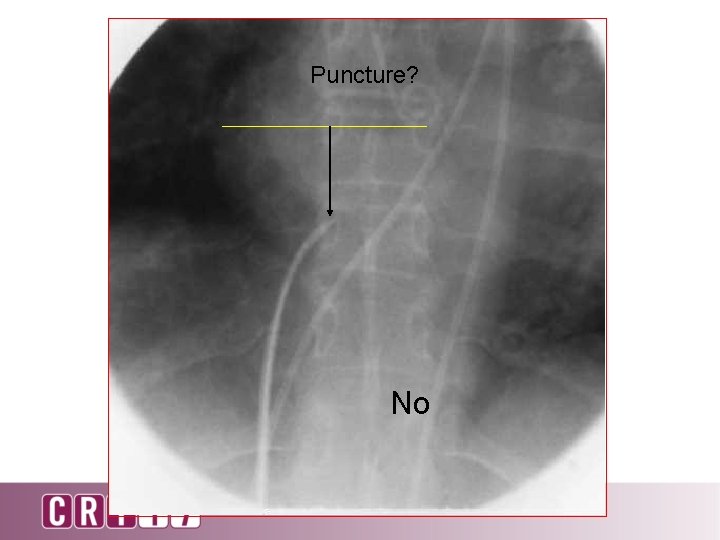

Puncture? No

Puncture? No